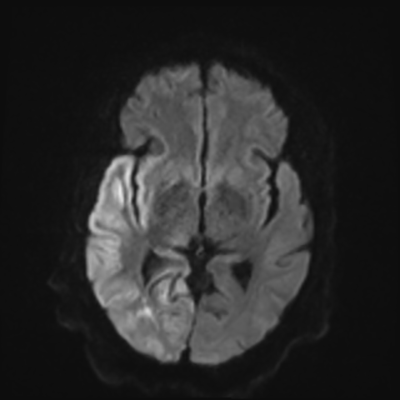

You come back the next day and see how things are going. The patient's electrographic record has shown a moderate encephalopathy (diffuse slowing, disorganization) with frequent right posterior quadrant delta slowing. Based on this result, and an adequately improved clinical examination, you give the okay to proceed with obtaining an MRI of his brain. This is shown below.

MRI brain (DWI)